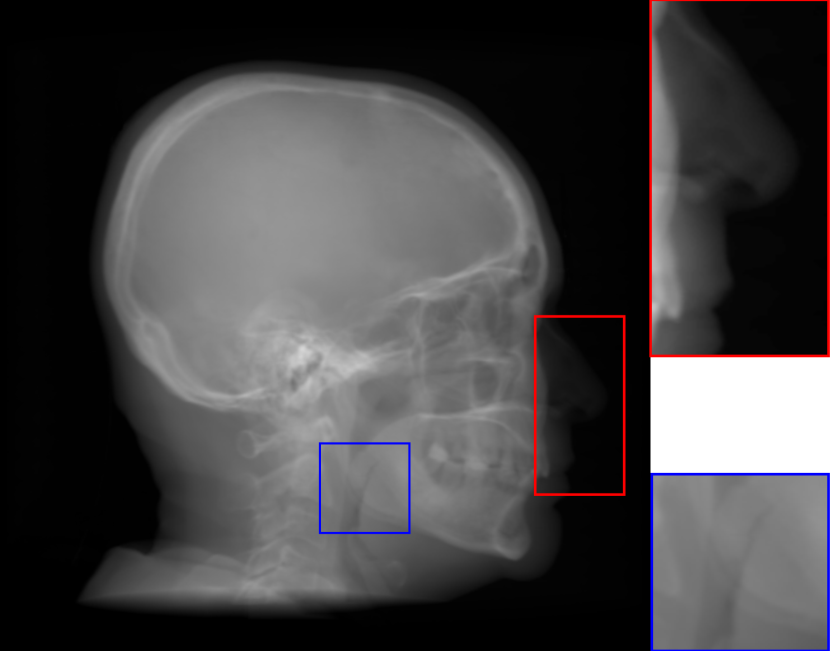

Fig. 8: Synthetic cephalogram examples from 3D CBCT volumes with different methods. (a)-(d) are comparison results while (e)-(h) are the (intermediate) results of our proposed method: (a) RayCast using orthogonal projection; (b) RayCast using perspective projection; (c) MIP using the largest 100 pixels along each orthogonal ray; (d) CycleGAN using patches from (a) and ISBI real conventional cephalograms; (e) RayCast using orthogonal projection from the skeleton enhanced volume; (f) original sigmoid transform of (e) using Eqn. (4) with air background recovery; (g) modified sigmoid transform of (e) using Eqn. (6), the final Type I synthetic cephalogram using orthogonal projection; (h) the final Type I synthetic cephalogram using perspective projection. The nose ROIs are redisplayed in the intensity window [0, 125] for better visualization. The mandible angle ROIs are for the visualization of the difference between orthogonal projection and perspective projection. The perceptual index of each synthetic cephalogram is displayed in the corresponding subcaption.

The synthetic cephalograms generated by different methods are displayed in Fig. 8. Figs. 8(a) and (b) show the cephalograms synthesized by the orthogonal [33] and perspective [21] RayCast methods, respectively, which are the most widely used methods for cephalogram synthesis from CBCT volumes. Comparing Fig. 8(b) to Fig. 8(a), due to different magnification factors of structures at different positions in perspective projection, anatomical structures on both sides of the midsaggital plane cannot overlap well, for example, the projections of the left and right mandible (gonial) angles in the zoom-in ROI in Fig. 8(b). In Figs. 8(a) and (b), the skeleton structures, soft tissues and airways are well observed. However, the image contrast in these two synthetic cephalograms are different from conventional cephalograms (Fig. 2(a)). The cephalogram synthesized by MIP using the largest 100 pixels along each orthogonal ray is displayed in Fig. 8(c). In this subfigure, skeleton structures are well observed since they have high intensity. Nevertheless, low intensity structures, e.g. the throat airway, might disappear. The CycleGAN [59] synthetic cephalogram is shown in Fig. 8(d). Compared with the conventional cephalogram example in Fig. 2(a), it has the closest image contrast. Hence, it achieves the best perceptual index of 5.53. However, some detailed anatomical structures are incorrect. For example, the nose has extremely low intensity in the zoom-in ROI. It also suffers from geometric distortion. As a consequence, the stitching artifacts are visible.

Figure 8(e)-(g) are the Type I synthetic cephalograms of different steps using orthogonal projection. Fig. 8(e) is the orthogonal RayCast celphalogram synthesized from the enhanced CBCT volume using Eqn. (1). Compared with Fig. 8(a), skeleton structures in Fig. 8(e) have higher contrast. Fig. 8(f) is obtained by applying the original sigmoid transform in Eqn. (4) to Fig. 8(e), where the skeleton structures are further enhanced. Moreover, the appearance of Fig. 8(f) is very close to conventional cephalograms. However, the soft tissues like the nose and lips have an almost constant intensity value, as displayed in the zoom-in ROI in Fig 8(f). The final Type I synthetic cephalogram with orthogonal projection is displayed in Fig. 8(g). With the proposed modified sigmoid transform in Eqn. (6), the contrast in the soft tissues is brought back, as displayed in the zoom-in ROI. For comparison, the final Type I synthetic cephalogram with perspective projection is displayed in Fig. 8(h). Compared with Fig. 8(g), the mandible angles in the zoom-in ROI of Fig. 8(h) are not overlapped well due to perspective magnification.